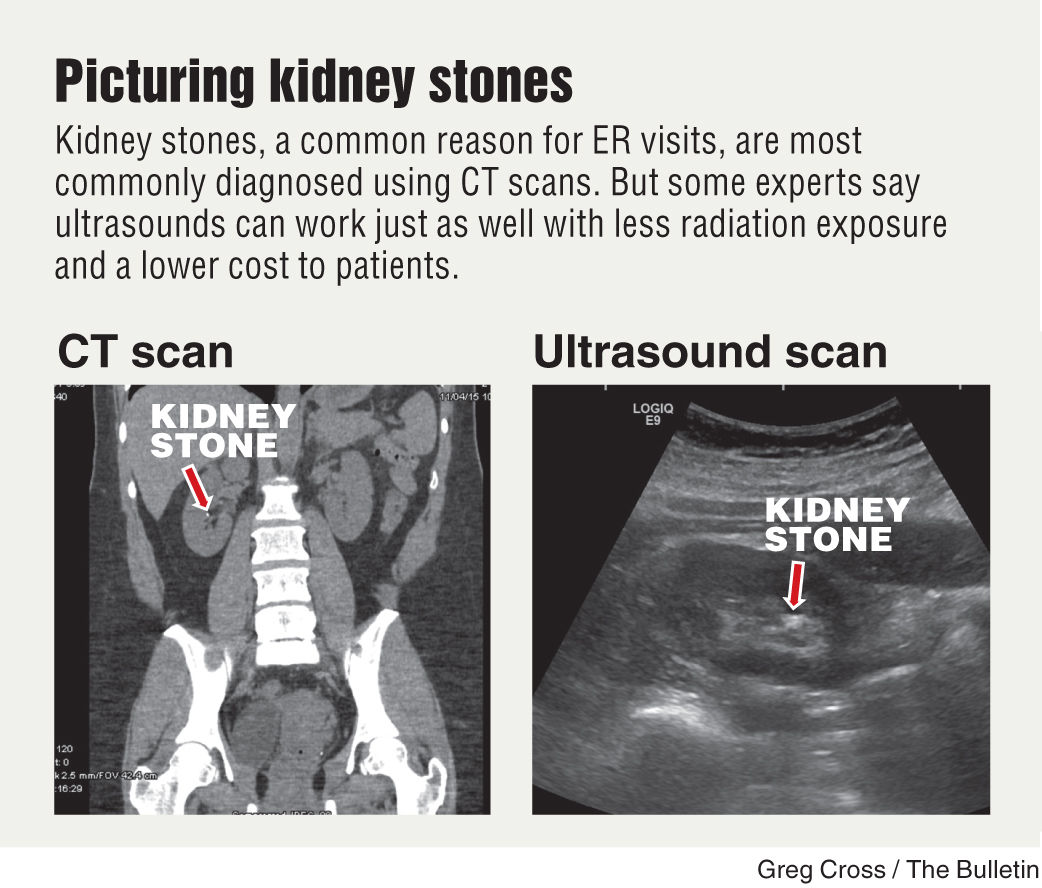

Can You Detect Kidney Stones With Ultrasound. A urine test can check for kidney. If you think you have kidney stones visit a doctor so they can perform a urine test ct scan or ultrasound to diagnose you.

Spiral ct scan is the most reliable imaging too.

Spiral ct scan is the most reliable imaging too. For more advice from our medical co author like how to treat kidney stones scroll down. A 45 year old member asked. Ultrasound can be efficient in visualizing clear uric acid stones and obstructions caused by any type of kidney stones.